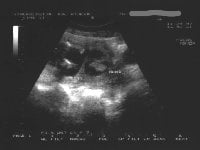

Amniyotik band sendromunda tanı ultrasonografik inceleme esnasında duvardan başlayıp kesenin içinde ilerleyen ve fetusda biten band şeklinde yapıların görümesi ile konur.Ayrıca etkilenen kısmın alt seviyelerindeki organ deformiteleri inceleme esnasında saptanabilir. Asimetrik deformite varlığında amniyotik band araştırılmalıdır.

Ayırıcı tanıda ise band gibi görülen amniyon zarı katlantılarına dikkat edilmelidir.